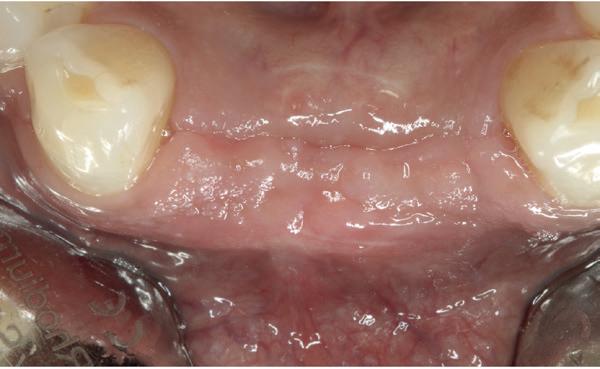

Vervaardigen essix retainer met dummies waarbij er een emergence profile van de 11 en 21 werd gevormd door eivormige dummies 4 mm in de gingiva te plaatsen

• Aanvulling zachte weefsels met de VISTA techniek en een vrij gingivatransplantaat uit het palatum links en direct dragen van de essix retainer

Na 4 weken intra-orale scan voor de etsbrug en kleurbepaling bij de technicus

• Plaatsen van de etsbrug met een composietcement

Voordat er gescand kon worden voor een etsbrug, werd een studiemodel vervaardigd om met de technicus te overleggen of er voldoende ruimte was voor 2 centrale incisieven in de mesio-distale zin en of er voldoende ruimte was in occlusie voor de vleugels van de etsbrug. Er hoeft enkel nog aan de 12 en 22 pala-

tinaal geslepen te worden als er geen 1,5 mm ruimte voor de vleugels behaald kan worden. De ruimte was op de dunste plekken 1 mm, dus een kleine preparatie in de 12 en 22 palatinaal was nodig. Omdat de kaak volledig afgevlakt was en dun was geworden, kunnen de dummies van de etsbrug enkel op de kaak “gelegd worden”, maar daarbij zijn er geen papillen en staat de cervicale rand van de dummies net voor de kaak. Een esthetisch resultaat kan daarmee niet behaald worden. Daarom is een aanvulling van de zachte weefsels in de breedte nodig, als het creëren van een emergence profile, waarbij het oogst alsof de gebitselementen uit het weefsel vertrekken.

Voor de aanvulling zachte weefsels chirurgie werd gekozen voor de VISTA techniek, hierbij worden er twee incisies partial thickness flap hoog in de mucosa gemaakt, waarna er ruimte vanuit de incisies wordt getunneld tussen de gingiva en het periost door middel van VISTA tunnel instrumenten. Uit het palatum links werd een vrij gingivatransplantaat geoogst van 15x10 mm met een dikte van 3 mm, die voor inhechten werd geëpithelialiseerd. Als het epitheel niet wordt verwijderd, kan deze graft door

de mucosa heen groeien, dat ten koste gaat van de esthetiek. In het donorgebied wordt een collageen spons ingehecht, waardoor de patiënt daar minder last van heeft. Het bindweefsel wordt door de hul-

pincisies met hechtingen naar het buccale en coronale deel getrokken en aldaar ingehecht. Met twee incisies werd ook de emergence profile gecreëerd (afbeelding 6-13). Voor een goede genezing van het

5. Beginsituatie voor behandeling

13. Occlusaal beeld verdikking van de zachte weefsels

14. Direct postoperatief plaatsen

van de essix met 2 dummy tanden